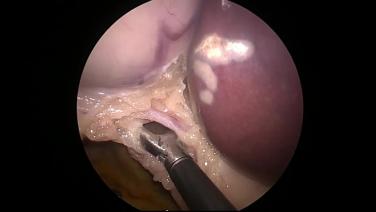

Laparoscopic Cholecystectomy - Transect Cystic Duct & Artery

Laparoscopic Cholecystectomy - Identify & Ligate Cystic Artery

Laparoscopic Cholecystectomy - Identify & Ligate Cystic Duct